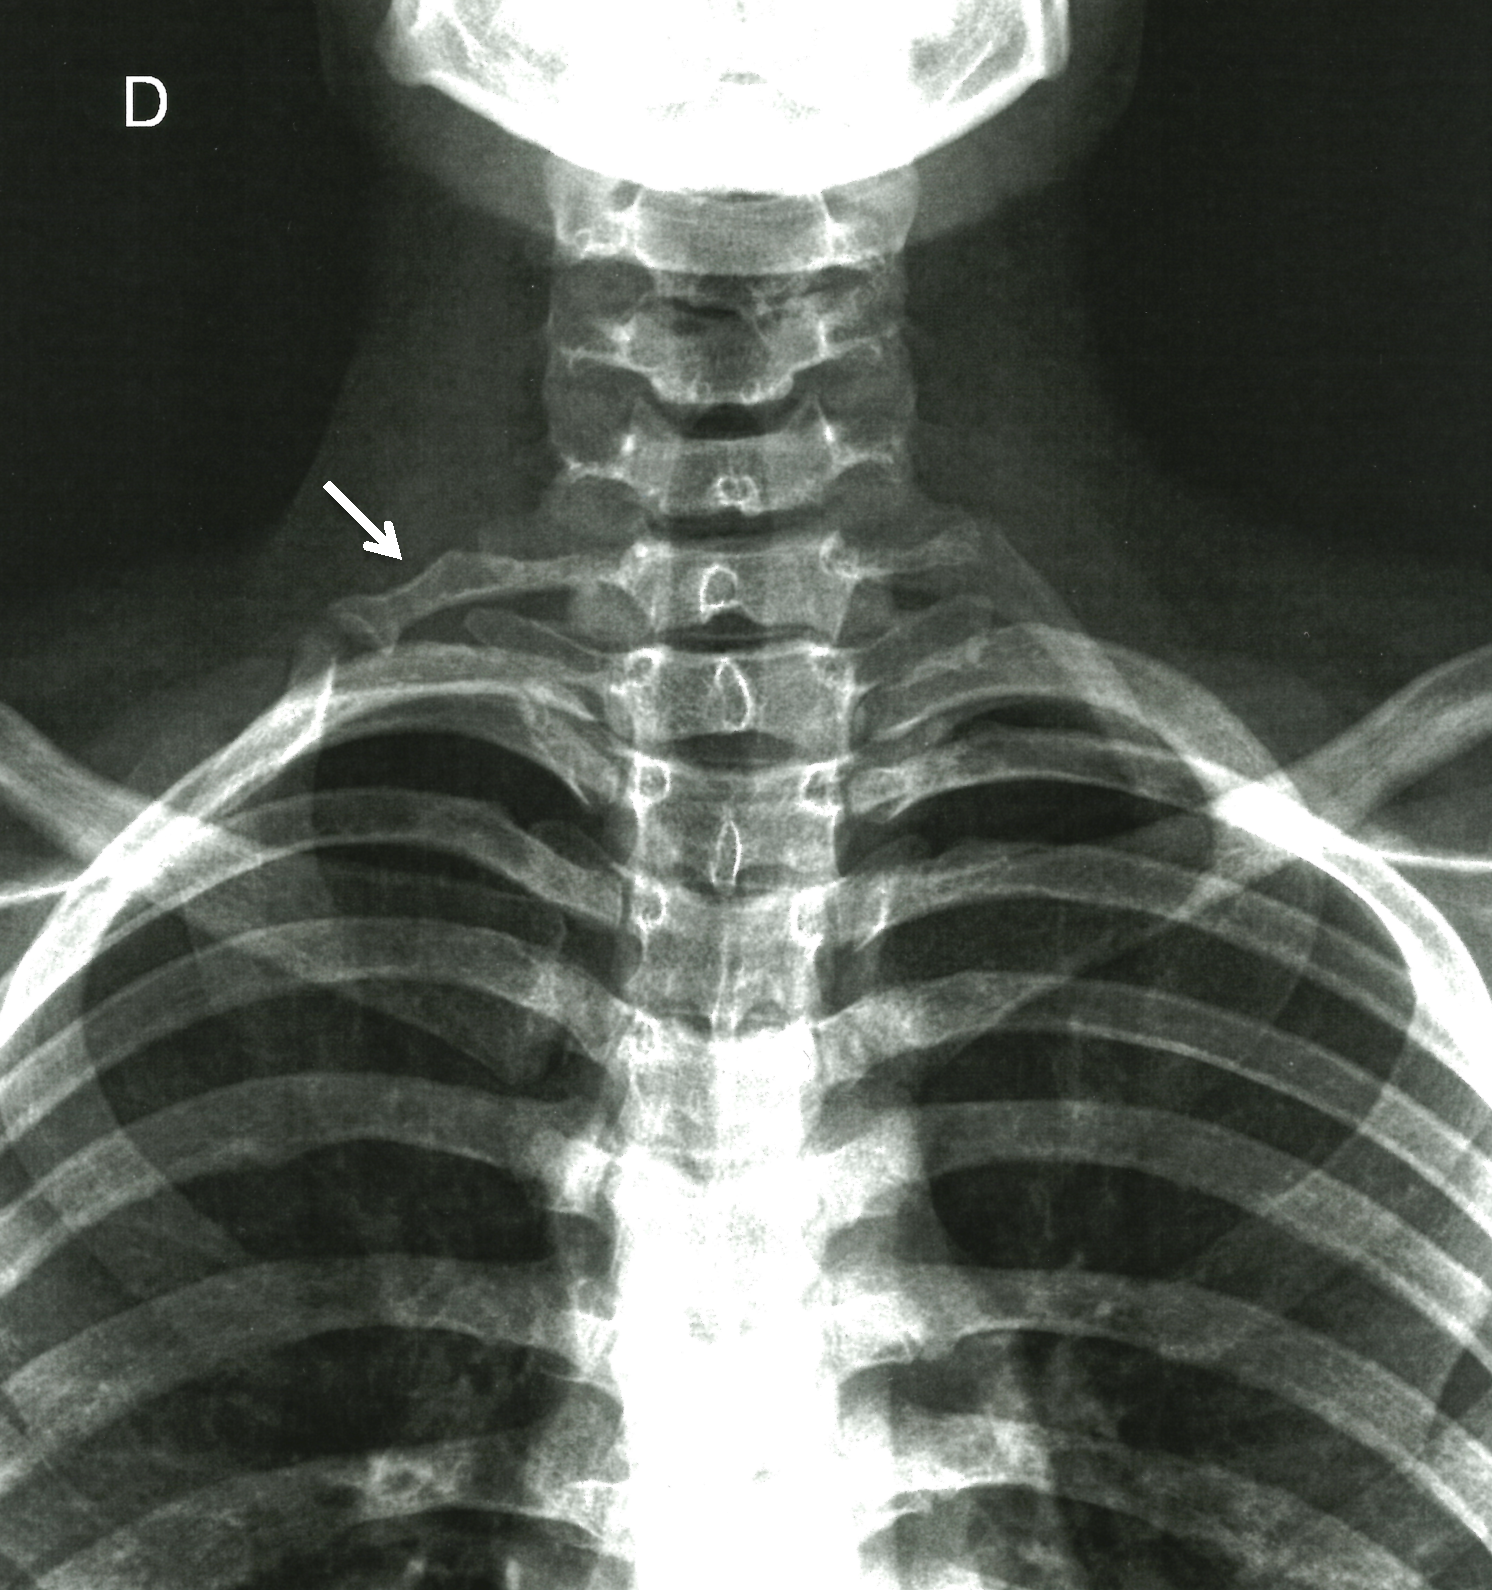

The hyperabduction maneuver (Wright test) showed no change in the radial pulse. The Adson test was also negative. Light percussion of the cubital nerve in the wrist caused a tingling sensation, which is a positive Hoffman sign. The cervical spine X-ray showed bilateral cervical ribs, more evident on the right side (Figure 1).

Figure 1. Anteroposterior X-ray film of the cervical spine showing bilateral cervical ribs more evident on the right side (arrow).